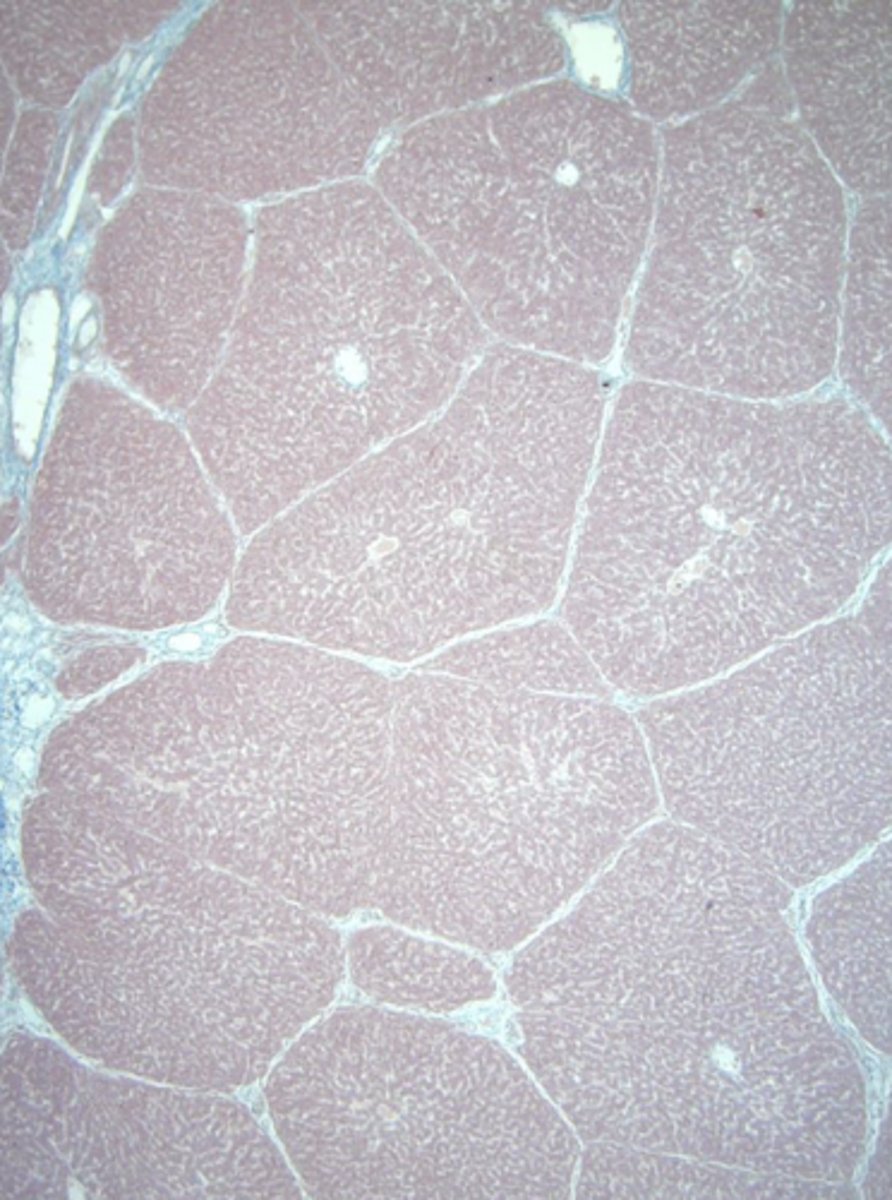

liver

name the tissue

lobule

(liver)

central vein

sinusoids

hepatocytes

type of cell